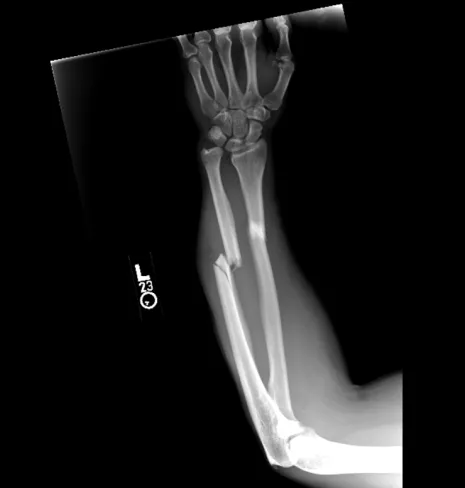

Bone injuries, known as fractures, are one of the most common reasons most people will visit an orthopedic surgeon. It is estimated that by 2025, in the US alone, 3 million fractures will occur every year. Some of this is driven by our aging population, but many of these occur in healthy young adults. In healthy individuals, fractures are usually related to higher energy trauma such as falls, sports injuries, and vehicle accidents.

At Pacific Crest Orthopedics, we customize a treatment plan to meet your individual needs. The fractures listed above are some of the most commonly seen, however, we treat all bone injuries. We put together a treatment plan depending on your type of fracture. Treatment can involve splinting, casting, or in some cases, surgical fixation. See more on our surgery treatments.